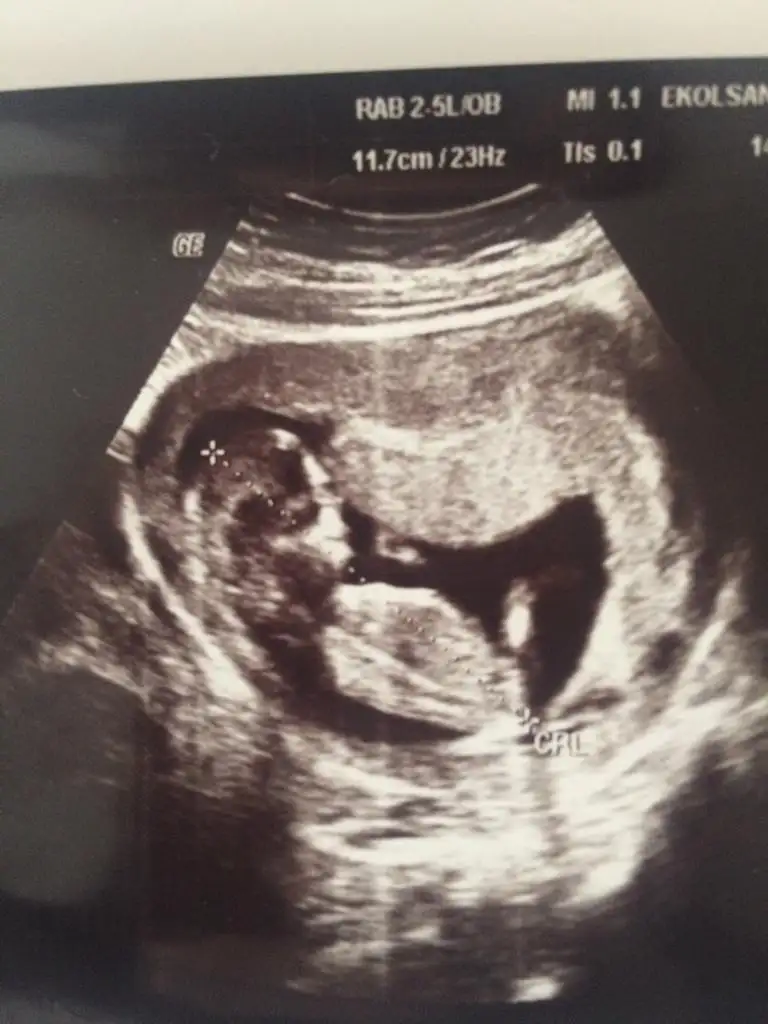

Yorum yapabilir misiniz erkek mi sizce

Bence kız bu bebiş

Ben Kıza benzettim